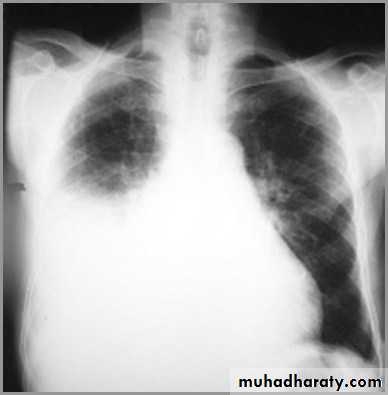

Differentiating the Causes of an Opacified Hemithorax

Atelectasis of an entire lungA large pleural effusion

Pneumonia of an entire lung

And a fourth cause: Post-pneumonectomy – removal of an entire lung

It acts like a massPushing the heart and trachea away from the side of opacification

pneumonia

The hemithorax is opaque and there isno shift of the heart or tracheaThere may be an air bronchogram sign present